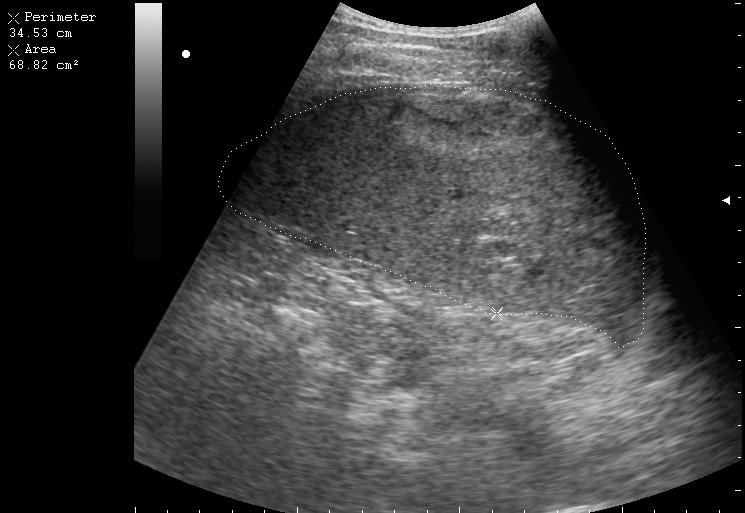

сегодня был селезёночный день.